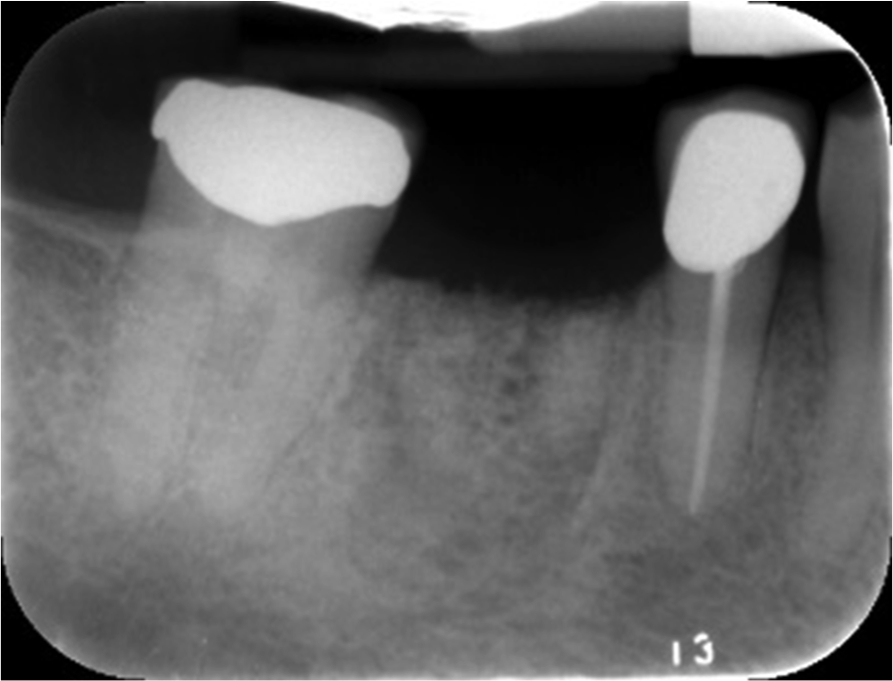

To obtain the maximum amount of information from the cone-beam computed tomography (CBCT) scan, a radiographic guide should first be fabricated. The periapical radiograph of the site where the tooth is absent can yield substantial insight into the approximate positioning that will be desirable for the implant(s). Figure 1 shows a case in which the patient wished to replace the missing right maxillary first and second molars with implant-supported restorations. The periapical radiograph revealed inflammation distal to the bicuspid root. In some cases, adjoining roots may impinge into the space to an even greater extent; it is important to avoid any perforation into the periodontal ligament.

Fig 1. Periapical radiograph revealing inflammation distal to the bicuspid root. Red lines help indicate location of each implant.

Figure 1